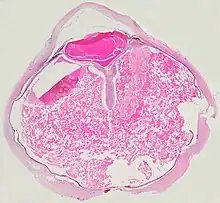

Grossly, retinal detachment and yellowish subretinal exudate containing cholesterol crystals are commonly seen.

Microscopically, the wall of retinal vessels may be thickened in some cases, while in other cases the wall may be thinned with irregular dilatation of the lumen.[10] The subretinal exudate consists of cholesterol crystals, macrophages laden with cholesterol and pigment, erythrocytes, and hemosiderin.[11] A granulomatous reaction, induced by the exudate, may be seen with the retina.[12] Portions of the retina may develop gliosis as a response to injury.